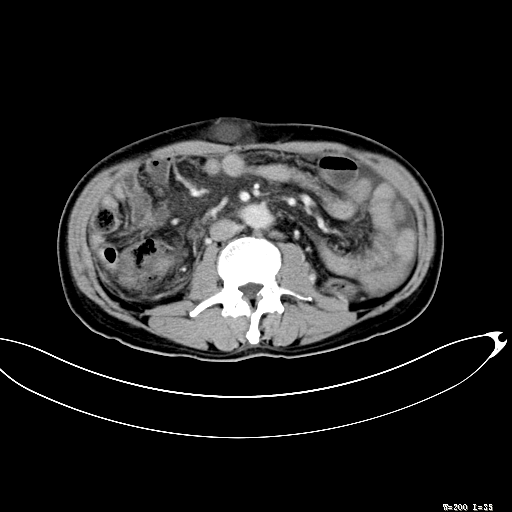

标题: CT27080:腹壁肿物?

男,52岁,门脉高压断流术后1年,发现腹部肿物2月。

1)前腹壁中线区(脐上方)囊性占位性病变,考虑淋巴囊肿。2)腹水。